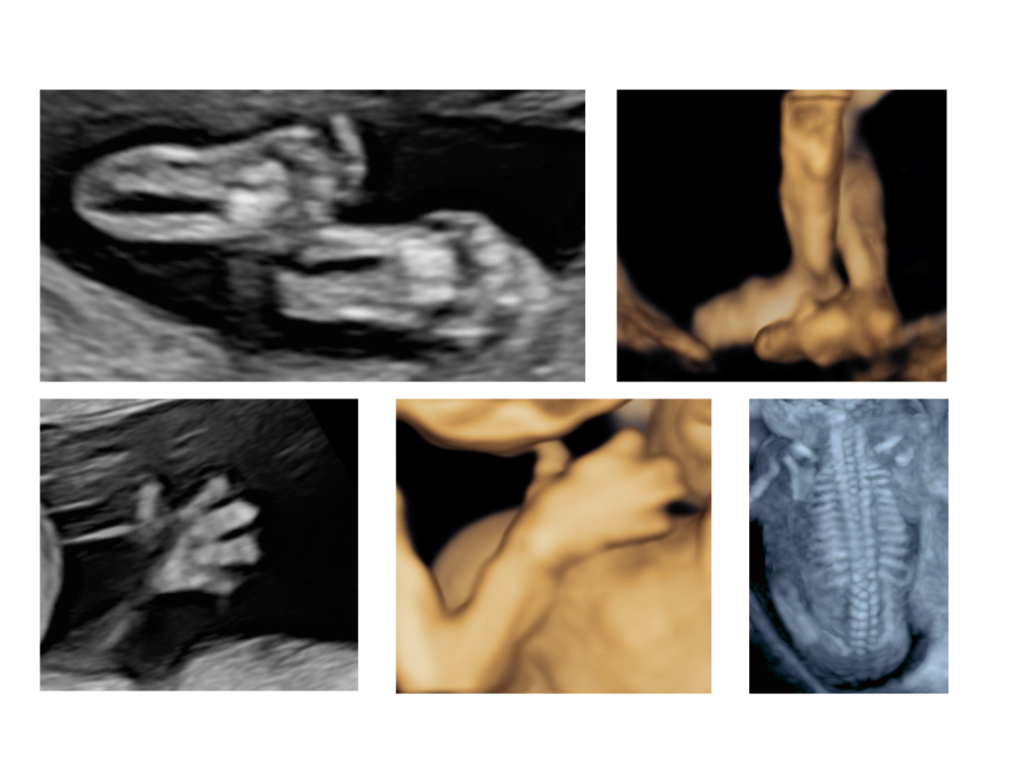

בדיקת אולטרסאונד המתבצעת בגישה בטנית, נרתיקית או משולבת – בהתאם לצורך. מטרתה היא לאתר מומים מבניים משמעותיים כבר בשלבים מוקדמים, כאשר רוב איברי הגוף כבר מפותחים וניתנים להדגמה.

בין האיברים הנבדקים: מוח, פנים, לב וכלי הדם הגדולים, ריאות, איברי הבטן (קיבה, מעי, כבד, כיס מרה, כליות ושלפוחית השתן), עמוד השדרה וגפיים עליונות ותחתונות.

סקירה זו מבוצעת לרוב בגישה בטנית, ולעיתים תתווסף גם בדיקה נרתיקית להשלמת ההדמיה.

נבדקות בה אותן מערכות שנבדקו בסקירה המוקדמת, לצד איברים נוספים אשר מתפתחים בשלבים מאוחרים יותר, וכן ניתן להבחין בפרטים קטנים יותר הודות לגדילתו של העובר.